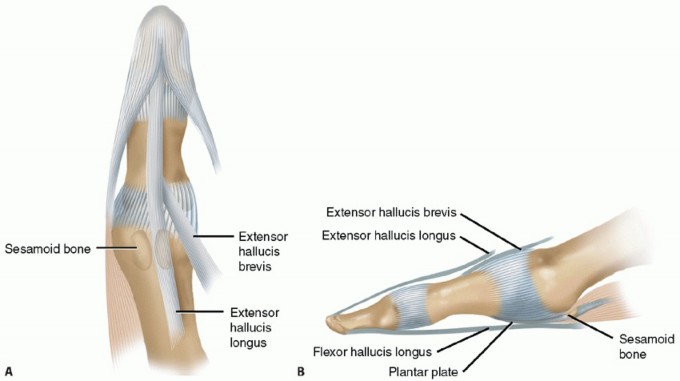

The bony anatomy of the first MTP joint includes the rounded first metatarsal head, which articulates with the concave, elliptically shaped base of the proximal phalanx.

Two longitudinal grooves separated by the crista, a central prominence, are located on the plantar surface of the metatarsal head. The two sesamoid bones contained in the medial and lateral tendon slips of the flexor hallucis brevis articulate with their corresponding longitudinal grooves on the inferior surface of the first metatarsal head. The flexor hallucis longus (FHL) tendon runs between the two sesamoids, bypassing the MTP joint to insert distally onto the distal phalangeal base.

FIG 1 • Anterior (A) and lateral (B) views of the first MTP joint.

The extensor hallucis brevis tendon inserts into the dorsal MTP capsule and the extensor hallucis longus runs distally to insert onto the distal phalanx.

The strong, fan-shaped collateral ligaments of the MTP joint originate medially and laterally from the metatarsal head and run distally and plantarward to the base of the proximal phalanx. The metatarsosesamoid ligaments fan out in a plantar direction to the margin of the sesamoid and the plantar capsule.

Distally, the two sesamoids are attached by the fibrous plantar plate to the base of the proximal phalanx, stabilizing the joint plantarly (FIG 1*).